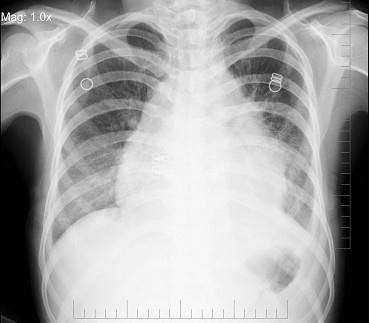

问题 女,24岁,干咳1个月出现胸闷气急,活动时明显,查体颈静脉显露,胸片如图,最可能的诊断为 ( )

选项 A.先天性房间隔缺损 B.心包积液 C.室间隔缺损 D.扩张性心肌病 E.法洛氏四联征

答案 B